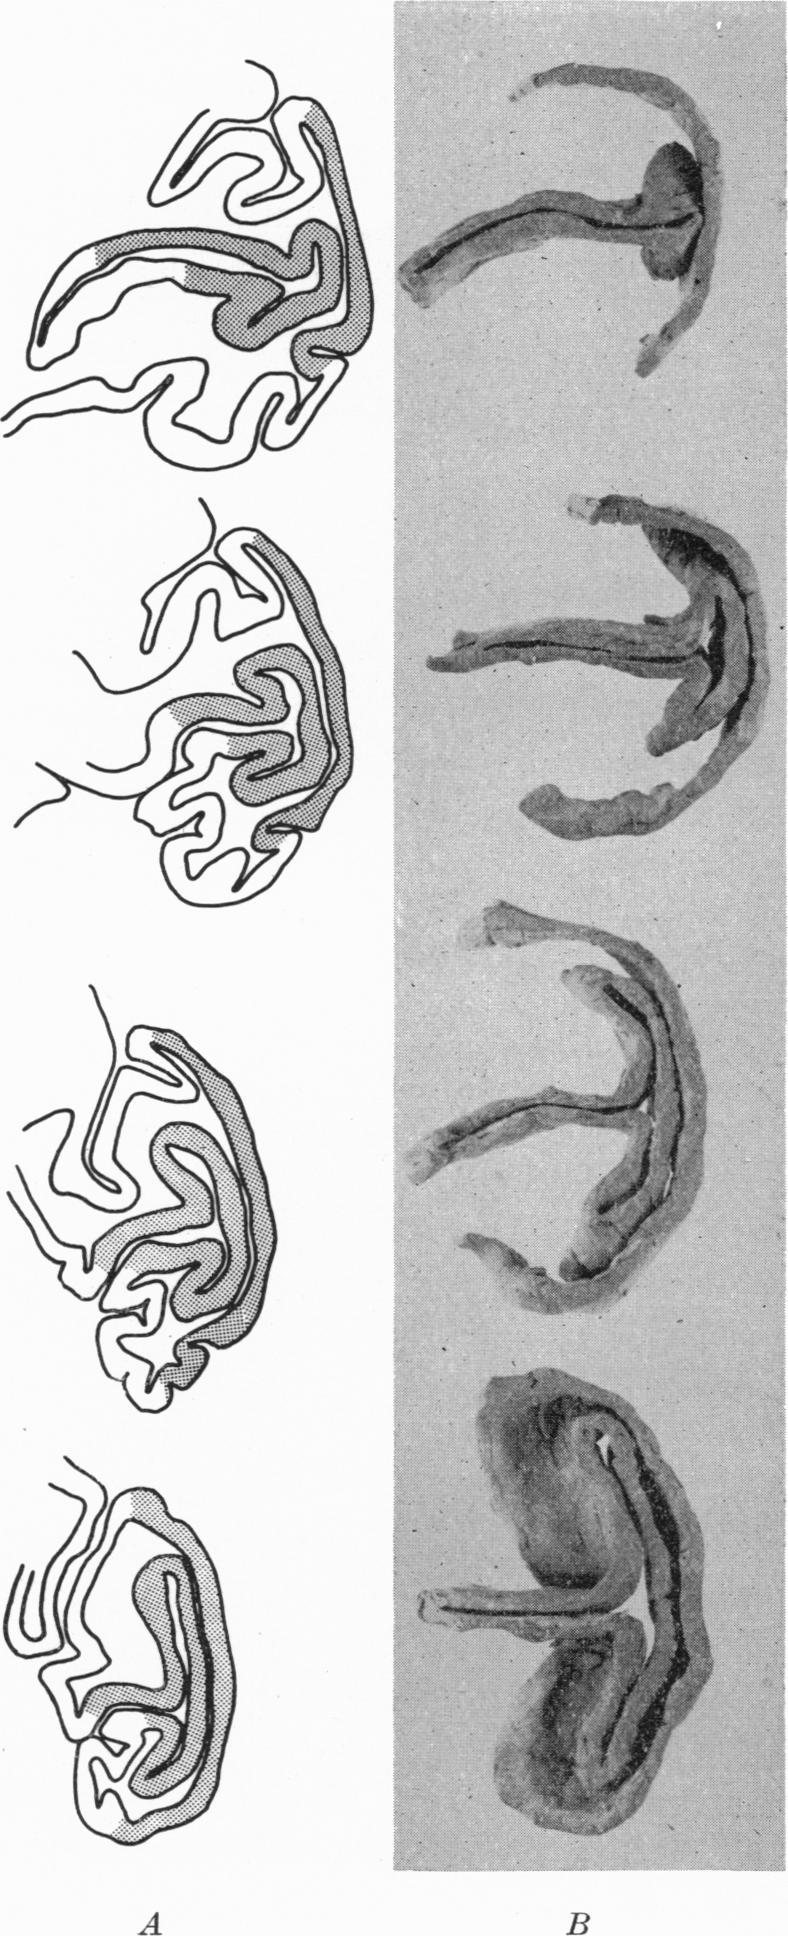

The representation of the visual field on the cerebral cortex in monkeys.

J Physiol. 1961 Dec;159(2):203-21. doi: 10.1113/jphysiol.1961.sp006803.